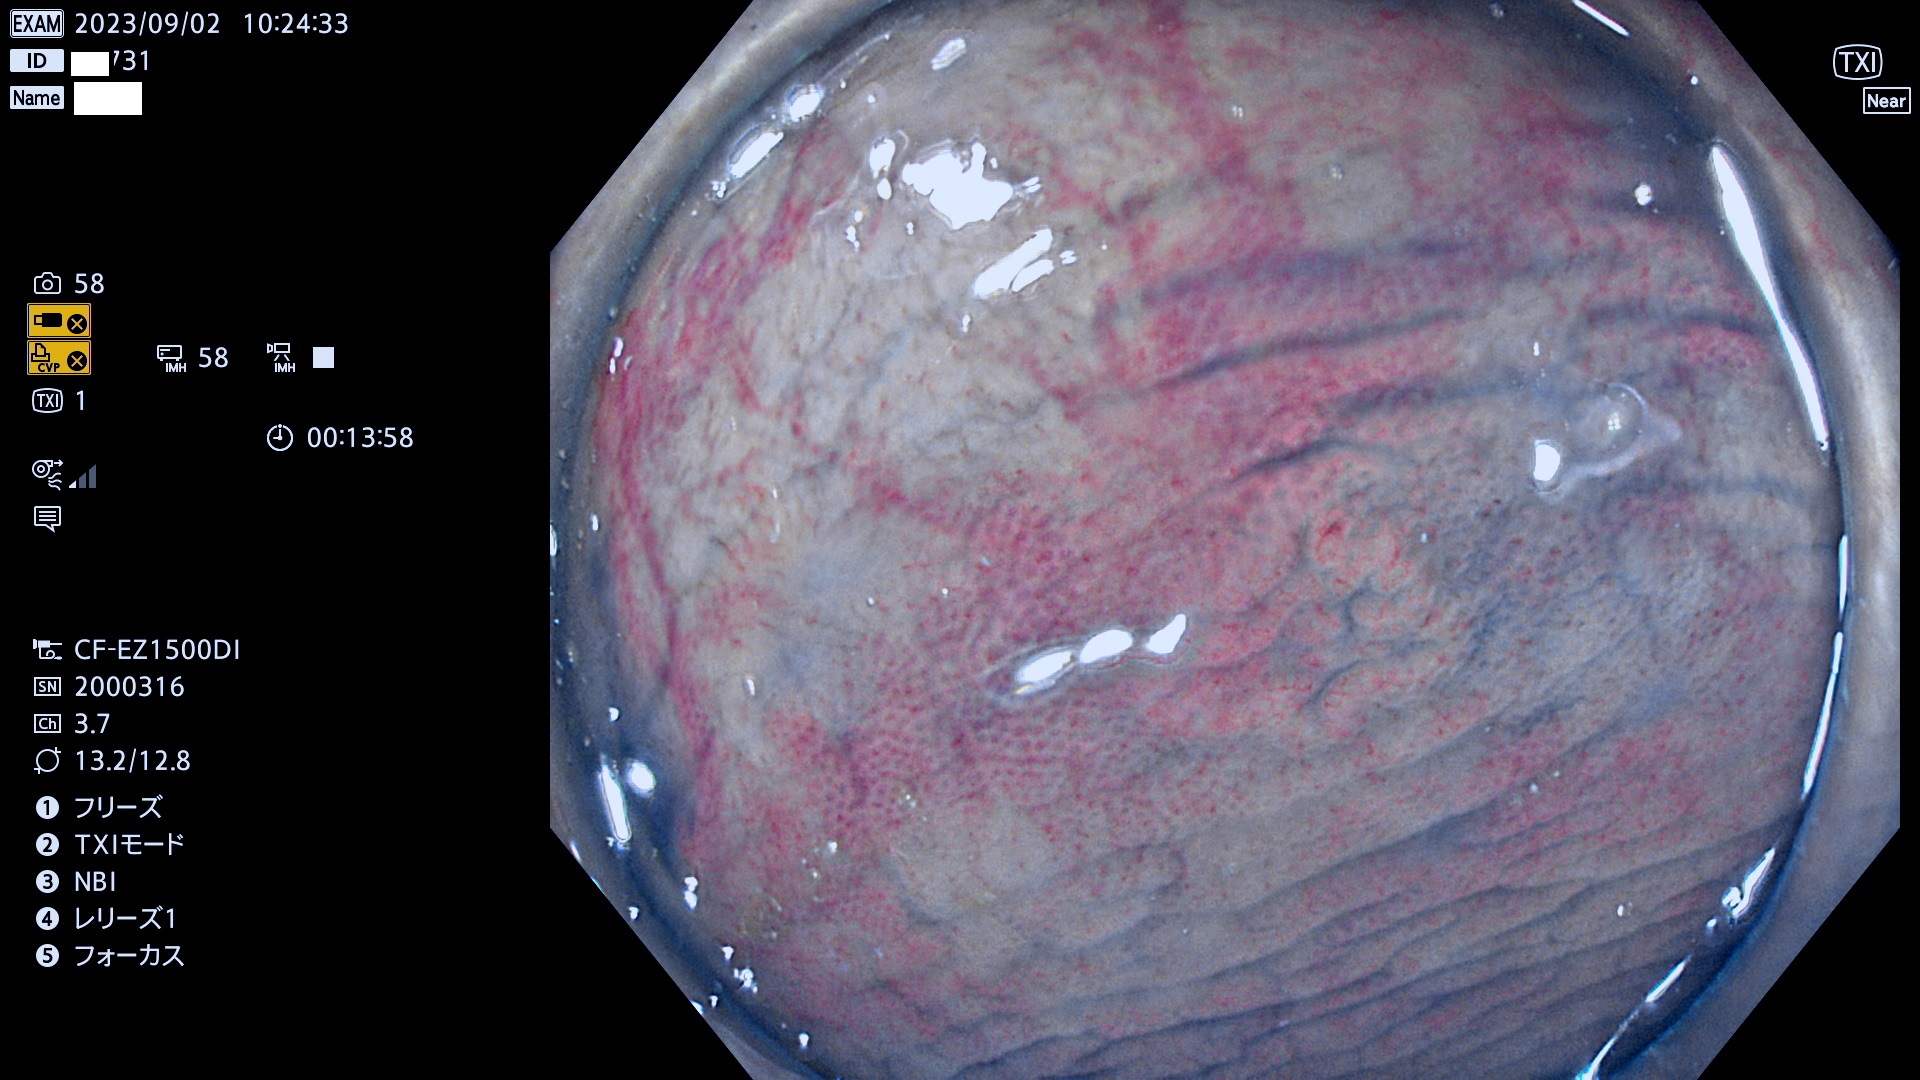

表面型腺腫(Flat Adenoma)の中で、完全に平坦な物をUb、陥凹している物をUcと呼びます。平坦隆起型(Ua)よりも、発見が難しく危険な病変です。このタイプは「内視鏡後・大腸癌の重要犯人」であり、この発見率は「腺腫発見率」よりも、重要な意味があります。

毎週の検査(木・金・土・日)に発見されたUb、Uc型・腺腫を、その週の日曜の夜にUPし1週間、提示します。

抽出の対象期間 2023年8月31日(木)〜9月3(日)の4日間(48件の検査)12件